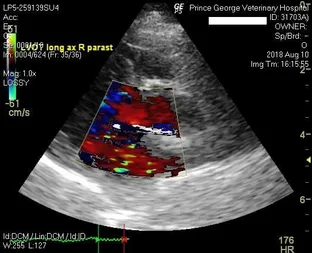

Echocardiography: Ultrasound of the heart

In order to be able to evaluate the inner workings of the heart in detail we offer echocardiography.